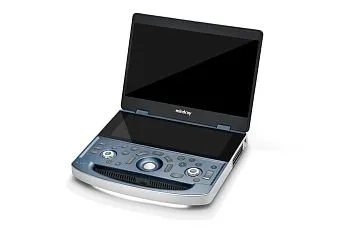

УЗИ аппарат Mindray MX7 портативный

УЗИ аппарат Mindray MX7 портативный

Mindray MX7 — высокотехнологичный портативный УЗИ аппарат, предлагающий впечатляющее качество изображения и широкий функционал. Благодаря своей компактности и мобильности, Mindray MX7 идеально подходит для работы в условиях ограниченного пространства или для выездных обследований. Портативный Mindray MX7 обладает передовыми технологиями, позволяющими получать четкие и детальные изображения в реальном времени. Благодаря различным режимам сканирования и широкому выбору датчиков, этот сканер может применяться в различных областях медицины, от акушерства и гинекологии до кардиологии и онкологии.

Приобретение УЗИ аппарата Mindray MX7 — надежное решение для клиник и врачей, которые ценят качество и точность диагностики. Надежность, мобильность и высокая производительность делают Mindray MX7 отличным выбором для специалистов, которым важны результаты и удобство работы. Вы можете заказать или купить со склада в наличии портативный УЗИ аппарат Mindray MX7 по выгодной цене, от надежного официального дистрибьютора Миндрей МСТ, с бесплатной доставкой в любой город.

Компактный дизайн и совершенная эргономика

- Вес 3 кг и толщина 44 мм (в сложенном состоянии) - сверхлегкая и тонкая портативная ультразвуковая система

- 15,6-дюймовый IPS монитор

- 12,3-дюймовый сенсорный экран обеспечивает пользователю интуитивно понятное управление

- Высокая мобильность и гибкость